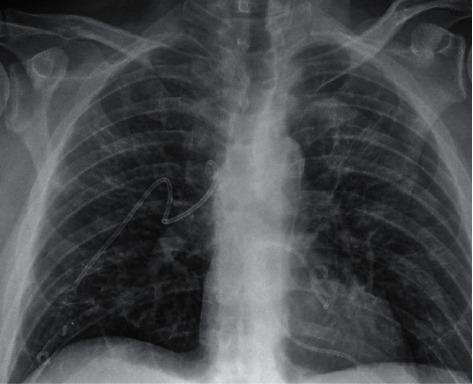

A 53-year-old male presented to the emergency room with chest pain, shortness of breath, and back pain. He had recently recovered from COVID-19 infection and returned home on room air. Chest imaging showed bilateral hydropneumothoraces that were not present on the imaging performed during his prior admission three weeks ago. The patient was treated with bilateral chest tube drainage and oxygen support and responded well to treatment. This case represents a unique occurrence of spontaneous loculated bilateral hydropneumothoraces in the context of recent clinical recovery from COVID-19 infection requiring inpatient treatment. This case highlights the importance of an awareness of a potential sequela of COVID-19 that may occur even after presumed clinical recovery.

一名53岁男性因胸痛、呼吸急促和背痛被送往急诊室。他最近从新冠病毒感染中康复,回家后仅呼吸室内空气。胸部影像学检查显示双侧液气胸,而三周前他上次住院时的影像学检查中并未出现这种情况。患者接受了双侧胸腔闭式引流和氧气支持治疗,治疗反应良好。该病例代表了在新冠病毒感染近期临床康复背景下发生的一种独特的自发性局限性双侧液气胸情况,需要住院治疗。该病例凸显了即使在假定临床康复后仍需意识到新冠病毒可能出现潜在后遗症的重要性。